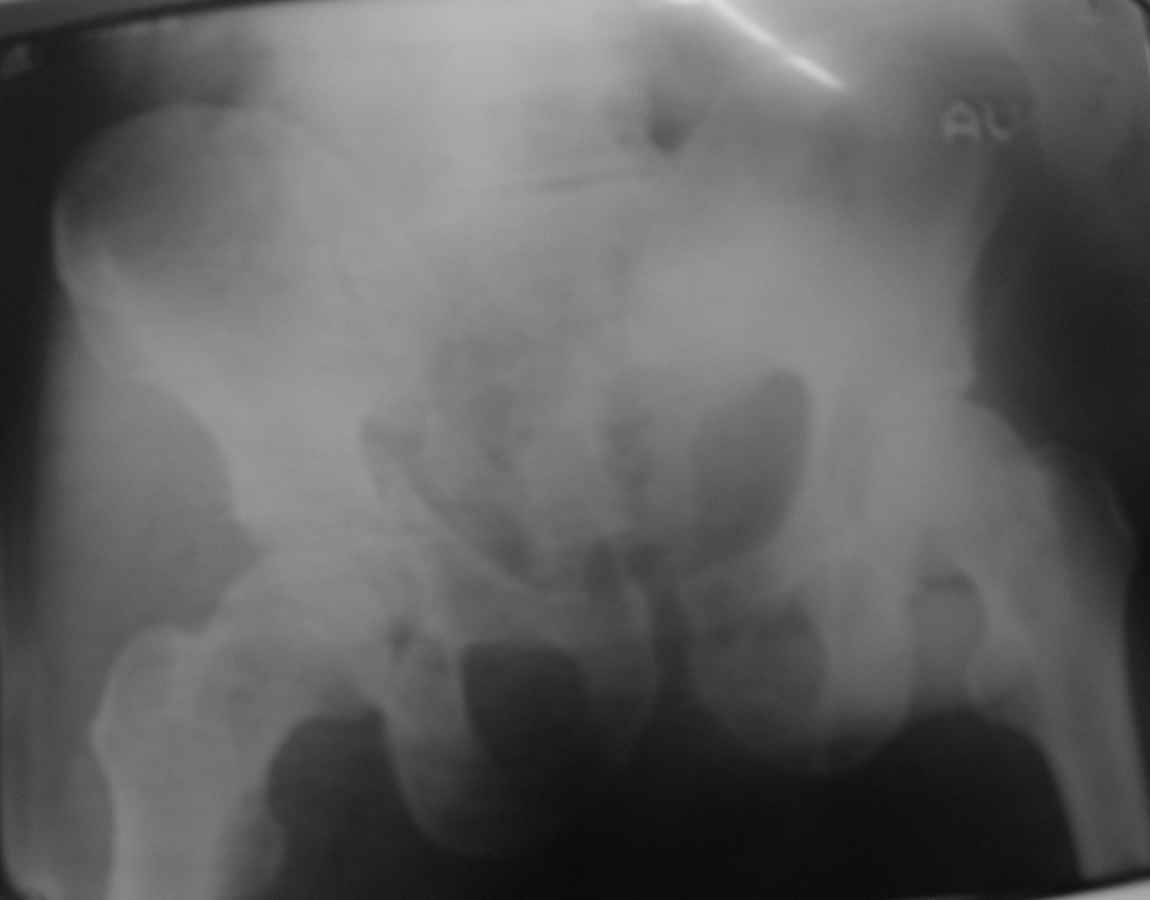

Уважаемые коллеги! Пациент 50 лет с переломом костей таза.

Ваши рекомендации по лечению.